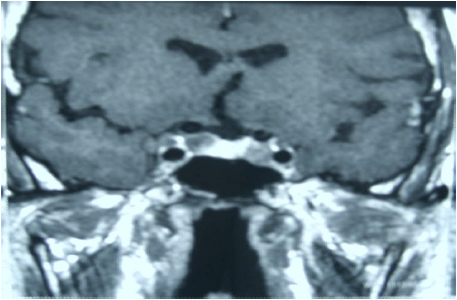

Observe a imagem de ressonância magnética, obtida em T1, plano coronal, e assinale a opção que indica o seguinte achado a ela correspondente: